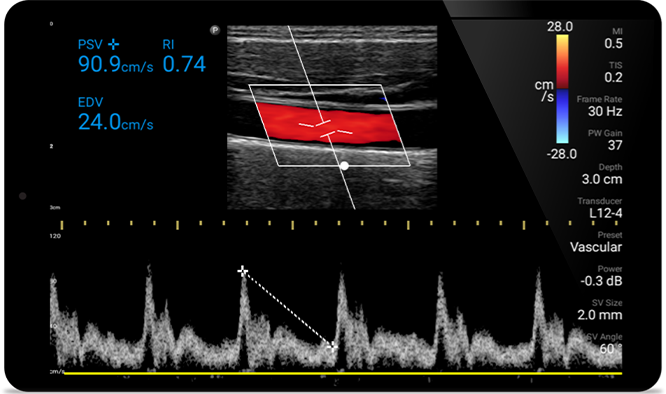

Lumify L12-4 broadband linear array transducer

From revealing the subtle details of an image to uncovering enriched tissue definition from multiple angles, Lumify can help you make real-time decisions with more confidence from assessment through recovery.

POC ultrasound for soft tissue